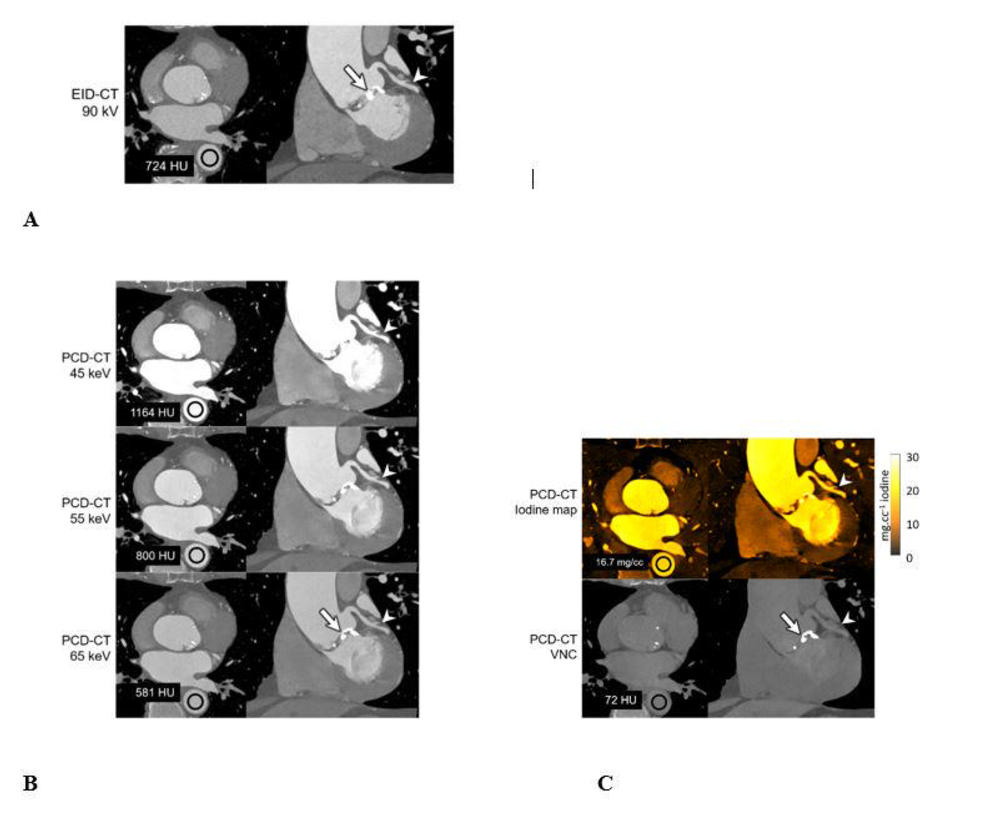

Figure 3. A 71-year-old male scanned on energy-integrating-detector (EID)-CT (A) and photon-counting-detector (PCD)-CT (B, C) with dual-source geometry to achieve 66-ms temporal resolution. Axial CT images are shown in the left column and oblique coronal images are shown in the right column. While the EID-CT exam is limited to single energy data (A) at this temporal resolution, the multi-energy capabilities of the PCD-CT system allowed creation of low energy (45, 55 keV) virtual mono-energetic images (VMIs) (B), which showed increased iodine signal (shown as mean HU measurements in region-of-interests) compared to EID-CT despite an 18% decrease (A: 110 mL versus B/C: 90 mL iohexol) in administered contrast volume (mean CT numbers for the regions of interest shown in black are given in the left column of images). The use of VMIs adds to the inherently higher iodine contrast-to-noise ratio possible with PCD-CT and provided clearer delineation of a branch of the left coronary artery (white arrowheads, right column). Increasing the VMI energy (65 keV or higher) decreased calcium blooming relative to EID-CT (white arrow, right column, A and B). Absolute iodine concentration was measured using the iodine map images (mean concentration in mg/cc unit shown in region-of-interest) and the virtual-non-contrast images used to visualize calcifications having similar attenuation to the iodinated blood (white arrow, right column, C). Reconstruction kernels used: Body-vascular (Bv) 40 (EID-CT 90-kV, A), Bv48 (PCD-CT VMIs, B), Quantitative-regular (Qr) 40 (PCD-CT iodine map and VNC, C). Display window/level: 2000/200 HU for EID-CT and PCD-CT VMIs, 30/15 mg.cc-1 for iodine map and 1000/100 HU for VNC image.